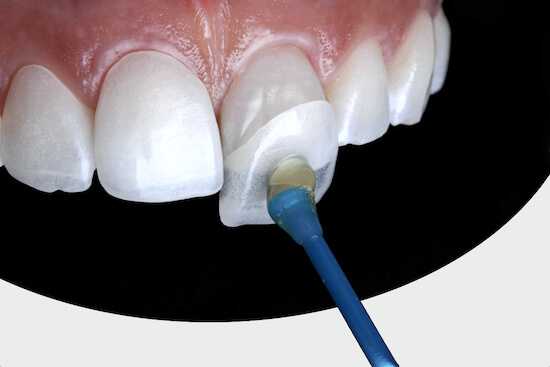

3. Лечение по технологии Icon . Это современный безболезненный метод лечения деминерализации и раннего кариеса без бормашины, который даёт хороший результат. Суть метода в том, что поражённые участки заполняются специальным веществом, которое благодаря капиллярному эффекту проникает в пористую эмаль, делает её плотнее, а также уничтожает кариозные образования и препятствует размножению патогенных бактерий.

Этапы лечения по технологии Icon.

- На поражённый зуб устанавливается изоляционная система типа коффердам, которая защищает зубы от влаги и позволяет врачу лучше видеть зону поражения.

- Наносится первый компонент — гель соляной кислоты (Icon-Etch), который открывает поры эмали. Его выдерживают 2 минуты, затем в течение 30 секунд смывают водой.

- Обработанная область продувается сухим воздухом.

- На 30 секунд наносится второй компонент — этанол (Icon-Dry), который удаляет остатки жидкости.

- Наносится третий компонент — текучая смола (Icon-Infiltrant). Её нужно выдержать 3 минуты. Затем остатки смолы аккуратно сдувают и материал «засвечивают» на протяжении 40 секунд, чтобы он затвердел.

- Излишки смолы удаляются полировочными штрипсами и флоссами, затем снимается коффердам [4][6][7][8] .